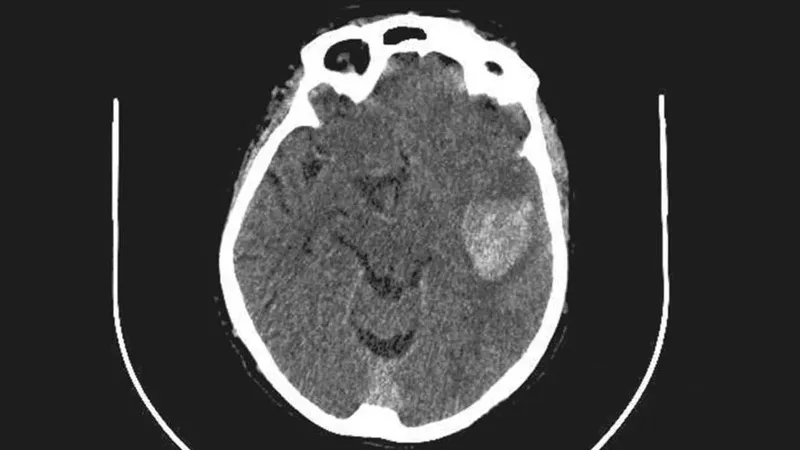

- Acute Ischemic Stroke (AIS)

- Symptom onset <4.5 hours.

- Disabling neurological deficit.

- CT excludes hemorrhage.

- BP <185/110 mmHg.

⭐ Intracranial hemorrhage (ICH) is the most feared and life-threatening complication of thrombolytic therapy.

- Most feared complication: Intracranial Hemorrhage (ICH); monitor for neurological changes.